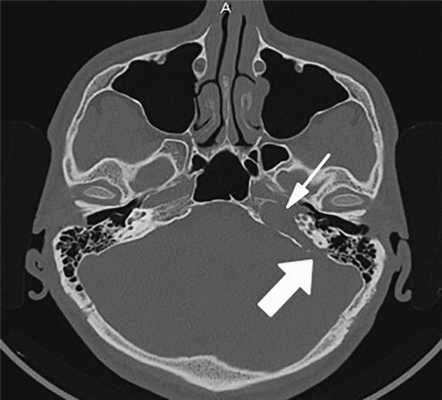

Рис. 1. КТ пациента с холестеатомой левой височной кости — деструкция костной стенки внутренней сонной артерии (маленькая стрелка), базального и среднего завитков улитки, задней грани пирамиды (большая стрелка).

По результатам МРТ/РКТ височных костей: левая височная кость тотально заполнена патологическим субстратом с поражением пирамиды. Имеются деструктивные изменения височной кости: задняя грань пирамиды разрушена на протяжении 10 мм, передневерхняя — протяженностью до 15 мм, нижняя поверхность — до 25 мм. Капсула лабиринта значительно разрушена на уровне базального и среднего завитков улитки. Костная стенка лабиринтной части канала лицевого нерва не прослеживается, стенка тимпанального и мастоидального отделов сохранена. Отмечалось разрушение стенки канала внутренней сонной артерии. После внутривенного контрастирования не было отмечено деформации стенки сосуда.